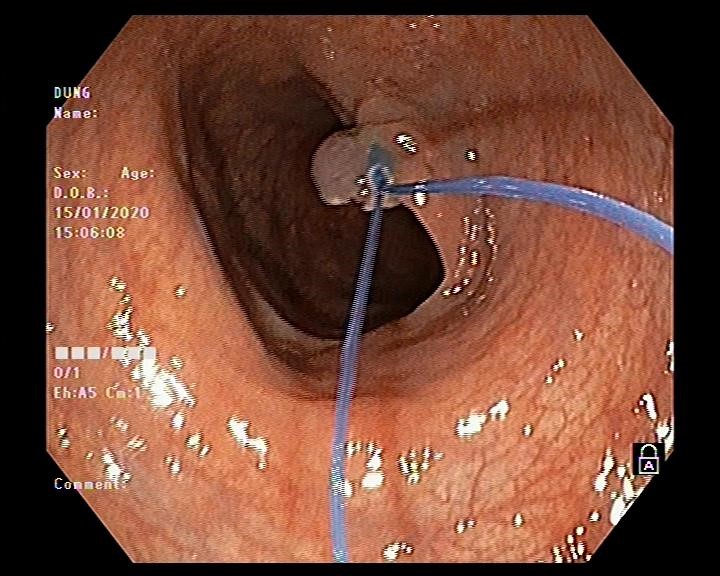

Hình ảnh thắt cuống polyp bằng vòng Endoloop

Vấn đề đặt ra là với kích thước và tính chất polyp như vậy thì có khả năng polyp được nuôi bằng mạch máu lớn, nếu chỉ cắt đốt bằng phương pháp thông thường thì nguy cơ xuất huyết ồ ạt sẽ rất cao. Do đó bác sĩ nội soi Ths Vũ Thanh Tùng quyết định sử dụng vòng Endoloop để thắt cuống polyp trước khi tiến hành cắt đốt. Thủ thuật diễn ra thuận lợi, nhanh gọn trong vòng 10-15 phút và không xảy ra tai biến dù là polyp này được nuôi bằng mạch máu lớn.

Kỹ thuật sử dụng vòng Endoloop để thắt cuống polyp lớn là một kỹ thuật được áp dụng tại Đơn vị nội soi Bệnh viện đa khoa tỉnh Hải Dương từ tháng 10 năm 2019. Với những tiến bộ trong các công cụ hỗ trợ nội soi hiện nay như Endoclips và Endoloops, nó đã trở nên an toàn hơn để thực hiện kỹ thuật nội soi cắt polyp cuống lớn. Cấu tạo của Endoloop gồm 2 phần: phần cán của Endoloop có cấu tạo gần giống như cán của thòng lọng, có bộ phận để đưa vòng Endoloop vào chân polyp, phần thứ 2 là vòng thắt được cấu tạo bằng chất dẻo đặc biệt có gắn thêm ống nhựa như một một cái khóa vòng thắt. Để ngăn ngừa chảy máu sử dụng dụng cụ Endoloop như một dây ga rô buộc chặt cuống polyp ở vị trí sát chân polyp trước khi tiến hành cắt bằng thòng lọng. Sau khi cắt polyp dụng cụ Endoloop vẫn còn lại vài ngày sau ở phần chân polyp cho đến khi phần này teo lại dụng vào lòng đại trực tràng.